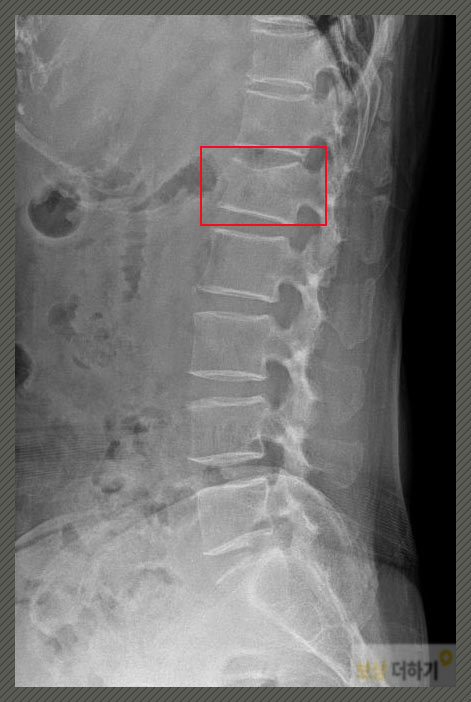

대부분의 사람들이 한 번쯤은 겪어봤을 법한 상황입니다. 단순 타박상 정도가 아님을 느끼셨고 병원에 가셔서 검사를 받은 결과, 허리뼈 1번이 손상되었습니다. L1 압박골절 S32020 즉 요추 1번 뼈가 찌그러진 형태로 골절이 된 것이었습니다.

수술 안 했는데 후유장해 남을까? 많은 분들은 "비수술이면 심각한 상태는 아니네" 라고 생각하시는데 절대 그렇지 않습니다. 위의 사진에서 보이듯이 척추뼈는 다른 신체 부위와 달리 네모난 모양인데요. 금이 가거나 부러지는 형태가 아닌 위아래로 찌그러지는 형태로 골절이 일어납니다. 시간이 가면 찌그러진 모양이 펴지면서 회복되는 것이 아니기 때문에 수술 여부에 상관없이 후유장해가 남는다고 보시면 됩니다.